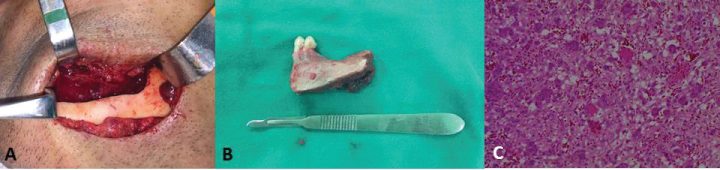

After the diagnostic confirmation, surgery was performed under general anesthesia for the marginal resection of the mandible with a margin of safety to avoid recurrence (Figure 3B). For such, an incision was made in the region of the posterior mandibular alveolar ridge and mucoperiosteal detachment to demarcate the area of resection to be performed with chisels and a mallet. A submandibular incision was also performed, and osteotomy was achieved with the use of a reciprocating saw (Figure 3A). The left mandibular first and second premolars were included in the area of the resection (Figure 3B, Figure 4A, Figure 4B and Figure 4C).

Figure 3: A) Submandibular surgical access with marginal osteotomy; B) Surgical piece of sectioned area; C) Histological cut revealing fragments of hypercellularized young connective tissue with intense monocellular inflammatory infiltrate, hemorrhagic exudate and multinucleated giant cells, confirming diagnosis of central giant cell granuloma. View Figure 3

Figure 4: A,B) Computed tomography reconstruction revealing area of resection; C) Panoramic radiograph after marginal resection. View Figure 4

The sample was sent for anatomopathological analysis, which confirmed the diagnosis of CGCG (Figure 3C). The sutures were removed after one week and the patient evolved with slight swelling, but no important complaints. At the six-month follow-up evaluation, the patient exhibited a normal facial contour (Figure 5A), small visible scar in the submandibular region on the left side (Figure 5B), an intraoral defect and the absence of the teeth involved in the resection (Figure 5C).